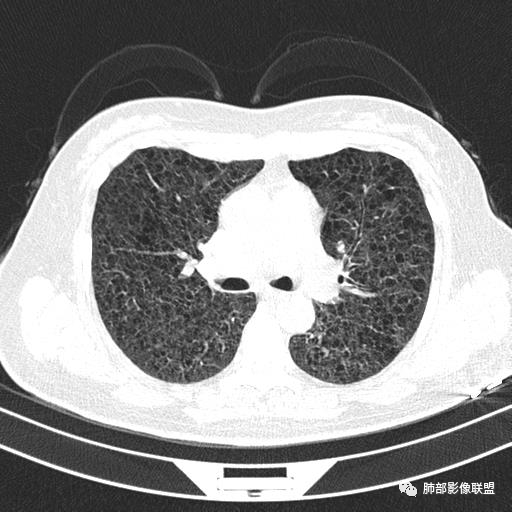

中年女性,不吸烟

双肺弥漫囊腔,累及肋膈角,囊腔形态相对规则单一。

CT平扫示双肺弥漫分布大小不等囊状薄壁透光区,无内、中、外带分布差异,间质稍示增厚。拟LAM

我也支持刘老师。中年女性,咳嗽气喘,有苯吸入史,双肺野多发囊腔,囊腔形态相对规则,大小不一,壁薄,有的似无壁,双肺弥漫磨玻璃影,有间质性改变,育龄期女性,首选考虑lam,但是患者有吸入苯病史半年,囊腔形态不是很规则,大小不一,分布不均匀,有的无壁似小叶中央肺气肿,有弥漫性磨玻璃及间质性改变,不排除吸入引起的间质性肺炎?

中年女性,双肺弥漫性磨玻璃密度影,并见弥漫性分布大小不一囊腔,壁薄,形态规则,考虑lam,鉴别苯中毒肺损伤致间质改变

中年女性育龄期妇女,咳嗽气喘,无吸烟史,有苯吸入史。影像:双肺弥漫均匀小囊腔,无明显分布优势,囊腔形态欠规则,壁薄,部分囊腔边缘血管征,伴双肺弥漫磨玻璃影,无结节,考虑lam,鉴别苯中毒肺损伤,囊腔多有分布优势,小叶中心分布为主,形态规整等

中年女性,两肺弥漫分布囊性低密度影,壁薄,相对规则,境界尚清晰,考虑LAM

中年育龄期女性,双肺多发含气囊腔弥漫性分布,囊间肺组织结构正常,常规考虑Lam

女,46,活动性气喘1年。苯吸入史半年。胸部CT:两肺弥漫囊腔,上至肺尖,下至肋膈角,形态类似小囊腔。考虑:LAM,鉴别LIP,BHD,PLCH等。

双肺弥漫大小不一薄壁含气囊腔,囊间肺组织正常,正常肺背景,肺尖肺底受累;青年女性,气喘,支持LAM

双肺多发大小相近的囊状影,分布趋势趋于一致,中年女性,考虑LAM。部分囊内见血管及分隔影,小叶中心性肺气肿代排

CT表现:双肺弥漫大小不等的薄壁囊腔,囊壁<2mm,外形规则,血管影多位于囊腔周围,囊腔之间肺组织正常,随着疾病进展到晚期,囊腔变大、增多,不可胜数,囊腔可融合成较大的囊,与肺气肿相似,形成间质性肺纤维化。部分病例可出现结节影。